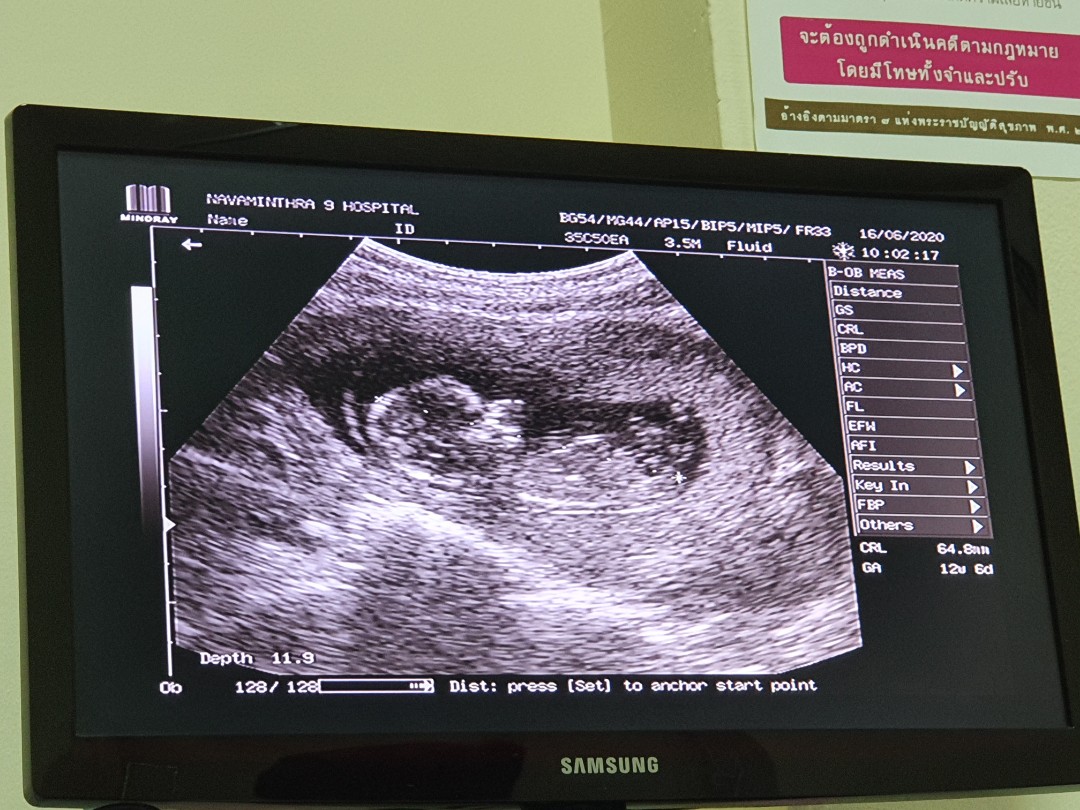

11 สัปดาห์ ซาวด์มาเจอลูกแบบนี้ถือว่าเขาตัวใหญ่ไหมคะหรือปกติ

บ้านนี้ตอน11w ค่ะ